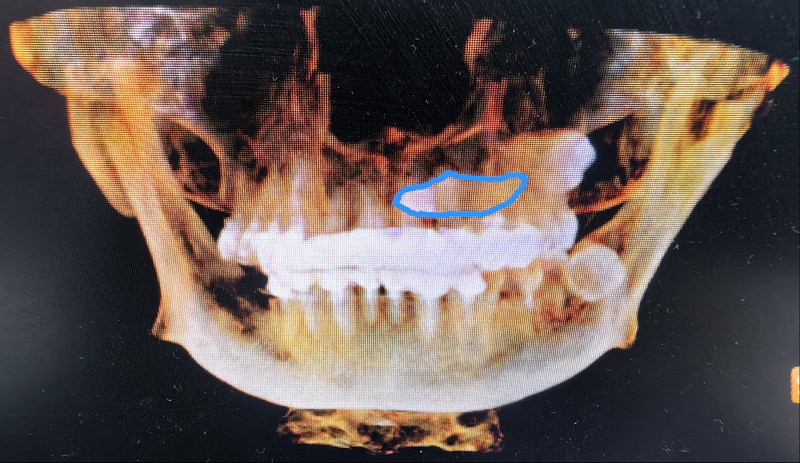

術(shù)前:尖牙橫行貫穿埋伏于左上頜骨內(nèi),牙冠位于上腭,牙根位于鼻根側(cè)下方。

劉弦醫(yī)生仔細(xì)查看口腔錐形束CT影像,發(fā)現(xiàn)這顆左上頜埋伏尖牙堪稱“定時(shí)炸彈”——碩大的牙根死死壓迫鄰牙,稍有拖延便會(huì)連累鄰牙不保。更棘手的是,這顆牙前臨鼻腔、后靠上頜竇,周?chē)p繞著鼻腭神經(jīng)血管束,拔除時(shí)稍有偏差,牙體就可能墜入鼻腔或上頜竇;面對(duì)謝女士“希望門(mén)診局麻下拔牙”的請(qǐng)求,這個(gè)手術(shù)難度堪比在精密儀器上“穿針引線”。